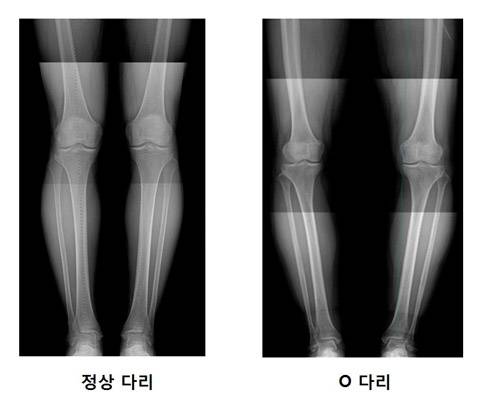

오다리는 다리가 ‘O자형’으로 휘어져 똑바로 서도 양측 무릎이 닿지 않는 상태를 말한다. 다리가 휘면서 내측으로 체중이 쏠리고 부담을 더 많이 받아 관절이 빨리 닳고 관절염도 악화시킨다.